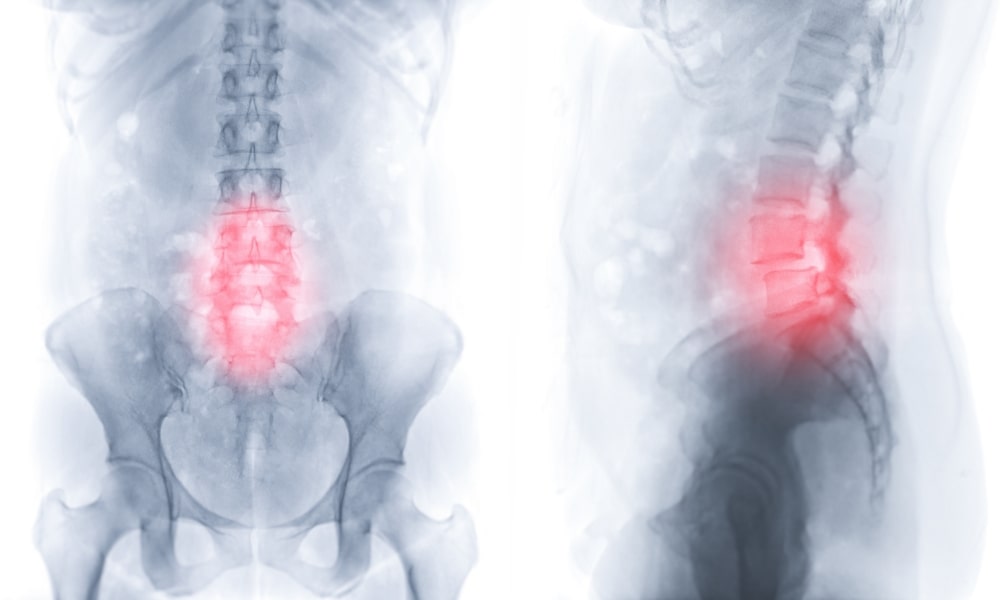

腰痛の原因

腰痛のタイプによって原因が異なります。

大きく分けると①筋肉の腰痛、②関節の腰痛、③狭窄症やヘルニアなどの病的な腰痛に分けられます。